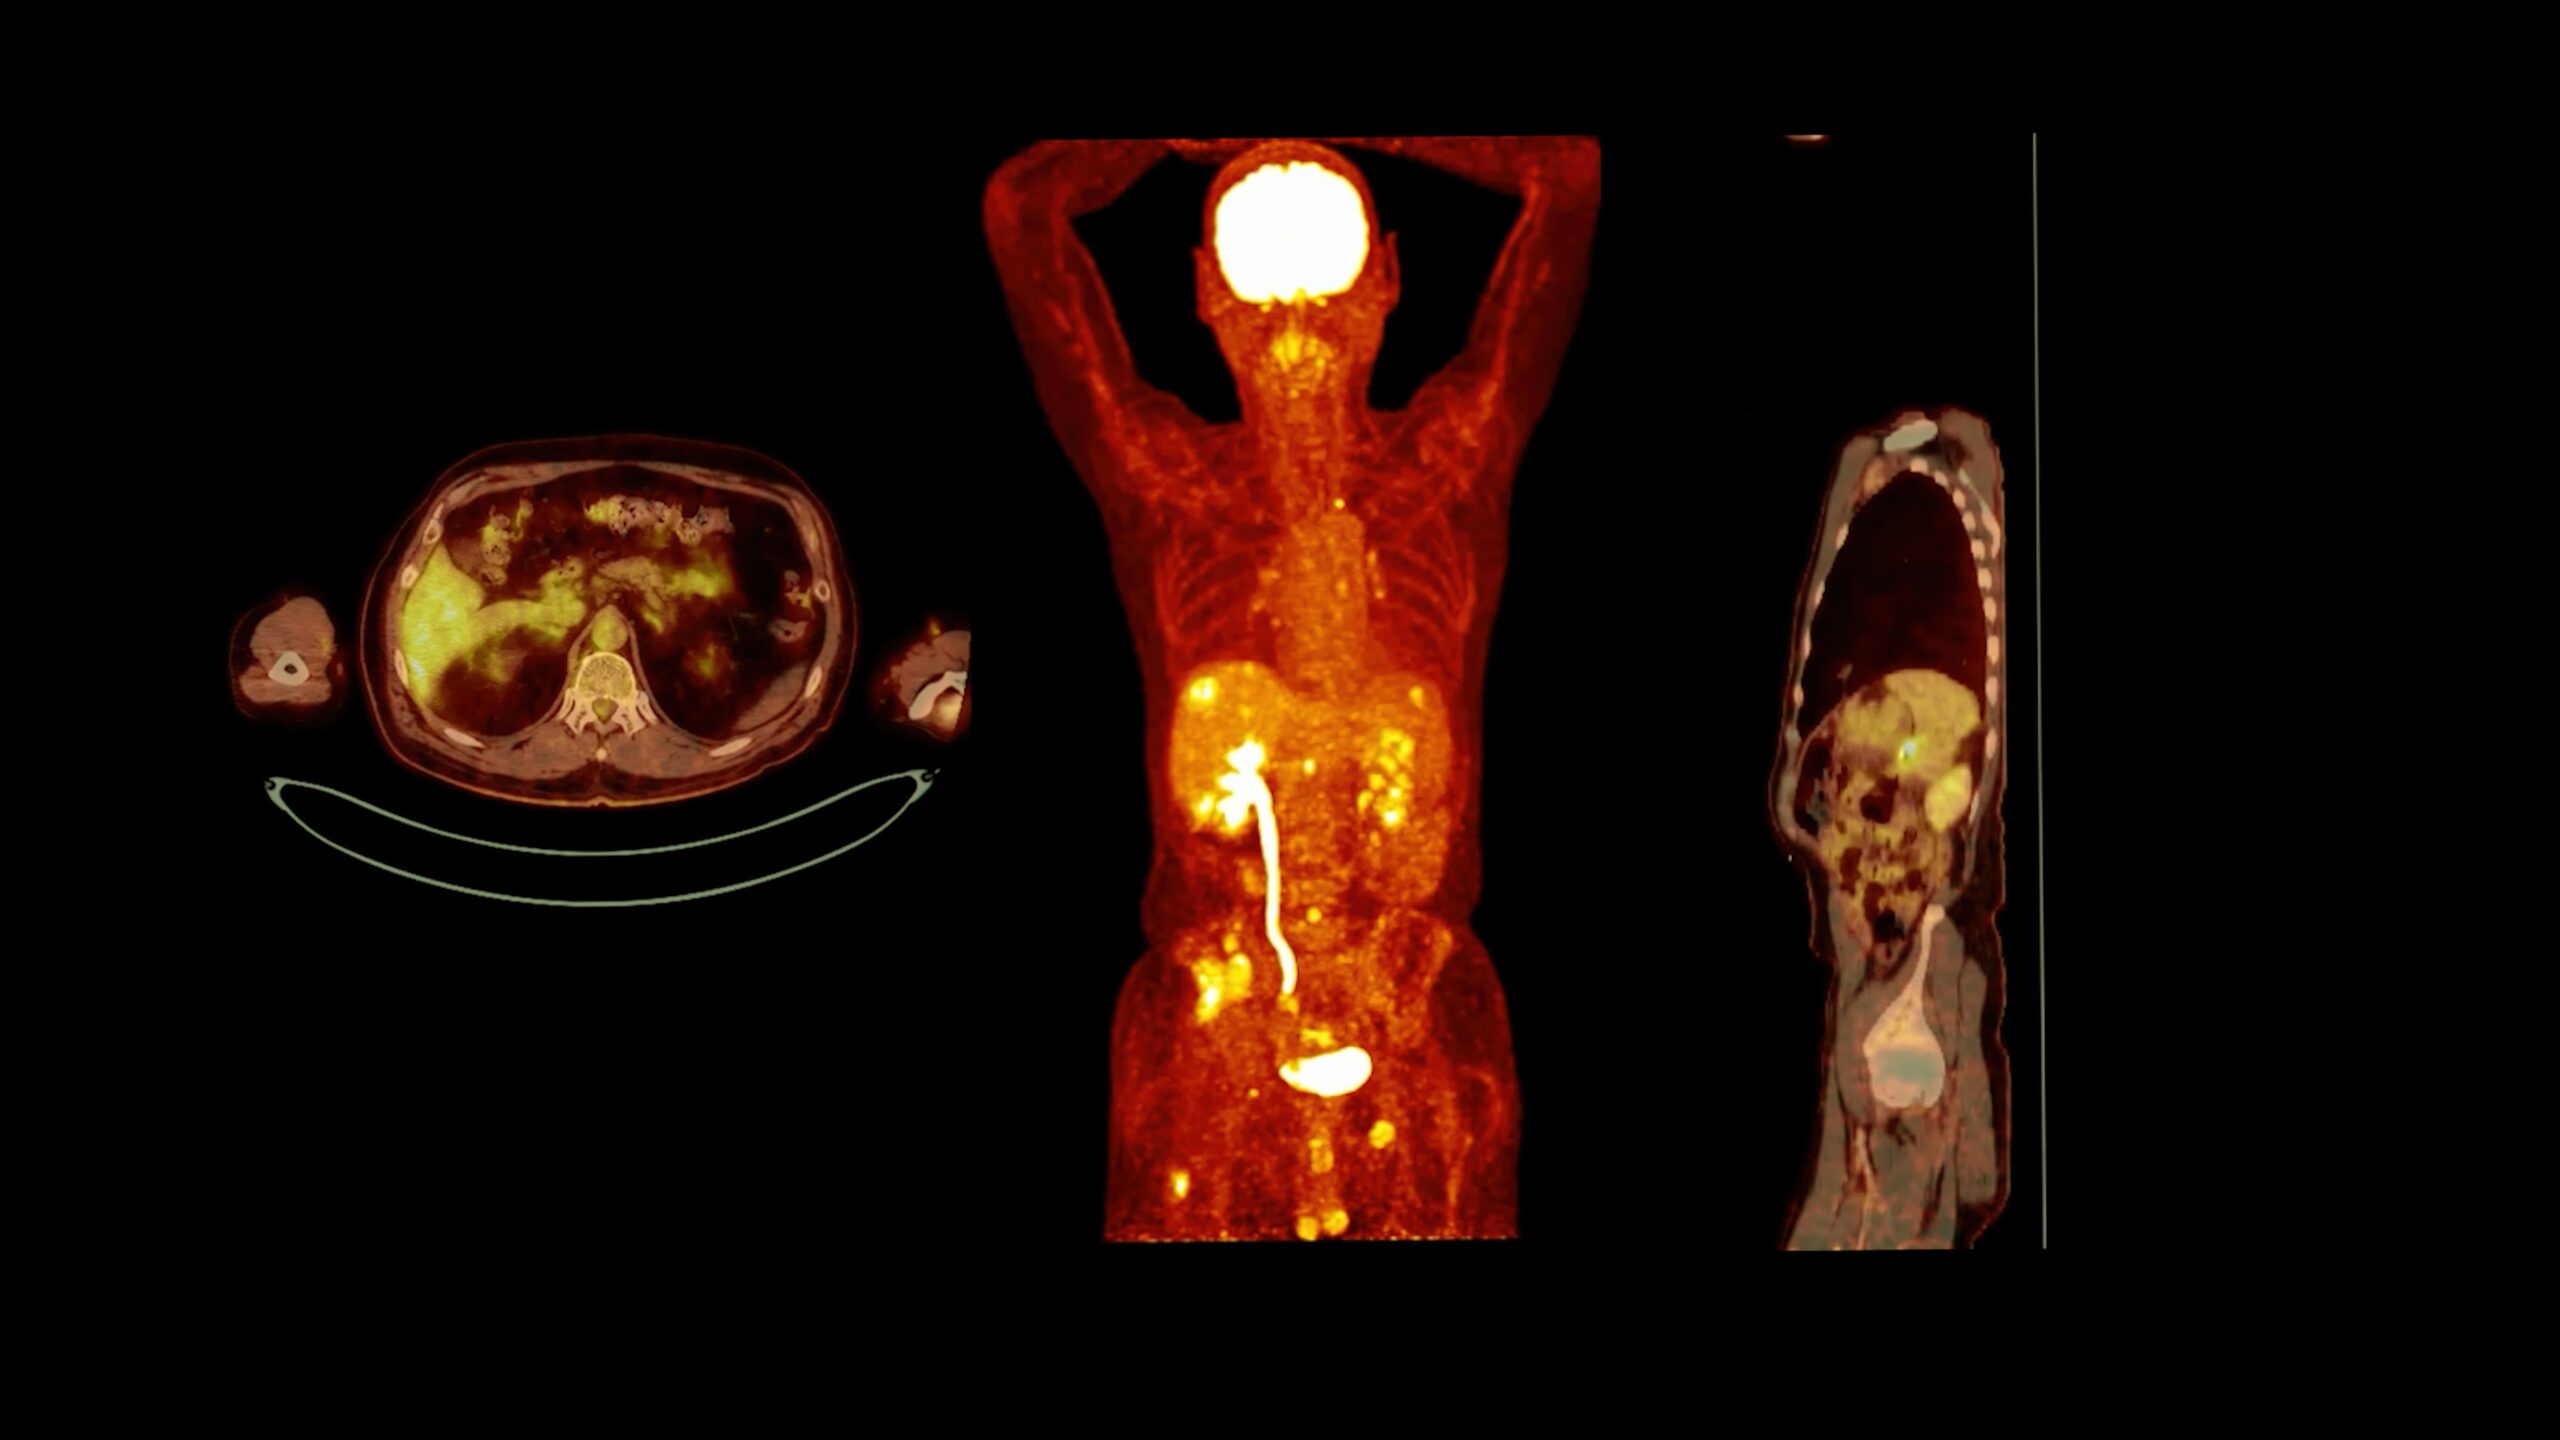

PET heart scans reveal how well your heart works, helping detect disease early and guide effective treatments.

POWERFUL DIAGNOSTICS FOR POSITIVE CARDIAC HEALTH

THE SCIENCE BEHIND PET HEART SCANS

PET scans measure heart metabolism to assess blood flow and tissue health. This technology helps detect coronary artery disease with exceptional accuracy.

HOW PET SCANS WORK

PET uses radioactive tracers that show how active the heart muscle is. This provides detailed insight into your heart’s energy use and function.